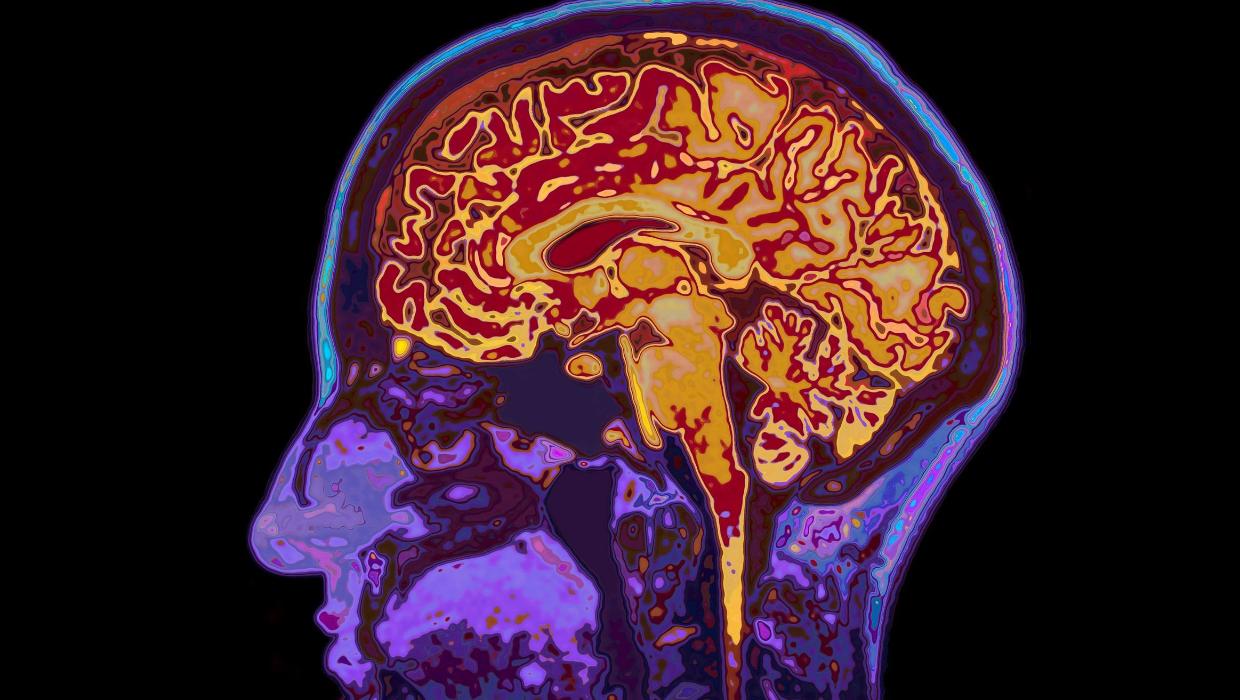

Study Reveals Brain Maturity Extends to Age 32, Aging Begins at 66

A recent study from the University of Cambridge has unveiled significant insights into brain development, revealing that the brain remains in a state of adolescence until the age of 32. The research identifies five major epochs of brain development and highlights four critical turning points throughout a person’s life, providing a deeper understanding of cognitive maturation and aging.

The groundbreaking study was conducted by a team of neuroscientists who meticulously analyzed brain development patterns in relation to age. According to their findings, the brain undergoes substantial changes from childhood through early adulthood, with the adolescent phase extending well into the third decade of life.

The researchers outlined five distinct epochs in brain development: early childhood, late childhood, adolescence, early adulthood, and maturity. Each of these stages is characterized by specific cognitive and emotional developments that shape an individual’s personality and decision-making abilities.

One of the most striking revelations is that while adolescence typically ends around the age of 18, the brain continues to evolve and mature until age 32. This extended period of development suggests that emotional regulation, impulse control, and social cognition are still maturing well into early adulthood.

In addition, the study indicates that aging begins at age 66, marking another pivotal turning point in brain function. During this stage, cognitive abilities may begin to decline, but the extent and nature of this decline can vary widely among individuals.